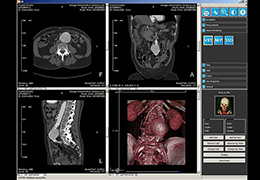

Traditional multi-planar slicing

High-quality and fast 3D reconstruction and 3D rendering

Performs 3D reconstruction and volume rendering.

Multi-planar slicing.

Oblique slicing.

Axis-aligned cropping with context.

Side-by-side comparative assessment for pre- and post-operative scans.